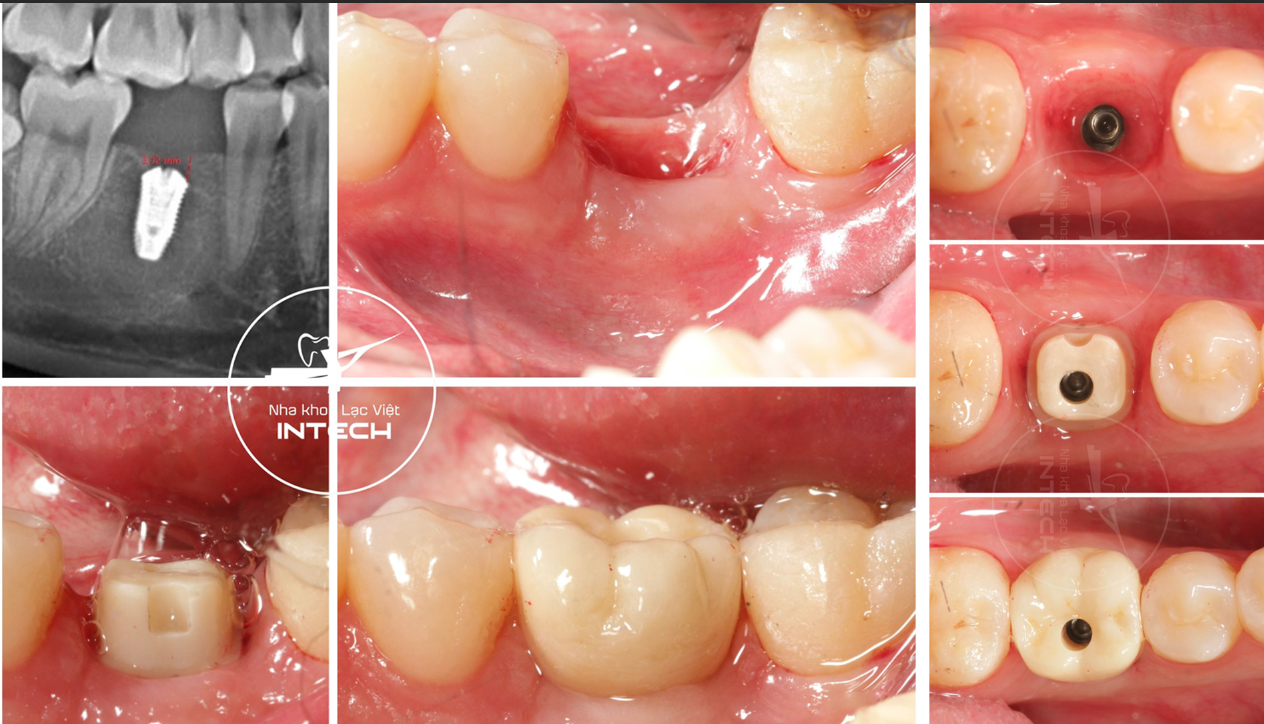

Trường hợp mất răng hàm được nha khoa Lạc Việt Intech điều trị bằng phương pháp cá nhân hóa DCT

Sau khi đánh giá đầy đủ và xác nhận đủ điều kiện thực hiện, bác sĩ sẽ tiến hành đặt trụ Implant vào vị trí răng đã mất.

Trụ Implant được đặt an toàn với vị trí, phương và hướng chính xác trong xương hàm

Sau khi trụ Implant hoàn toàn tích hợp xương, bác sĩ sẽ tiến hành lắp trụ phục hình và mão răng sứ lên trụ Implant và hoàn tất quy trình trồng răng Implant

Trụ phục hình được thiết kế cá nhân hóa theo cấu trúc giải phẫu của mỗi người, được lắp trên trụ Implant khi đã hoàn toàn tích hợp xương

Mão răng sứ cá nhân hóa có độ trong mờ và độ cứng như răng thật, được lắp bên trên trụ phục hình